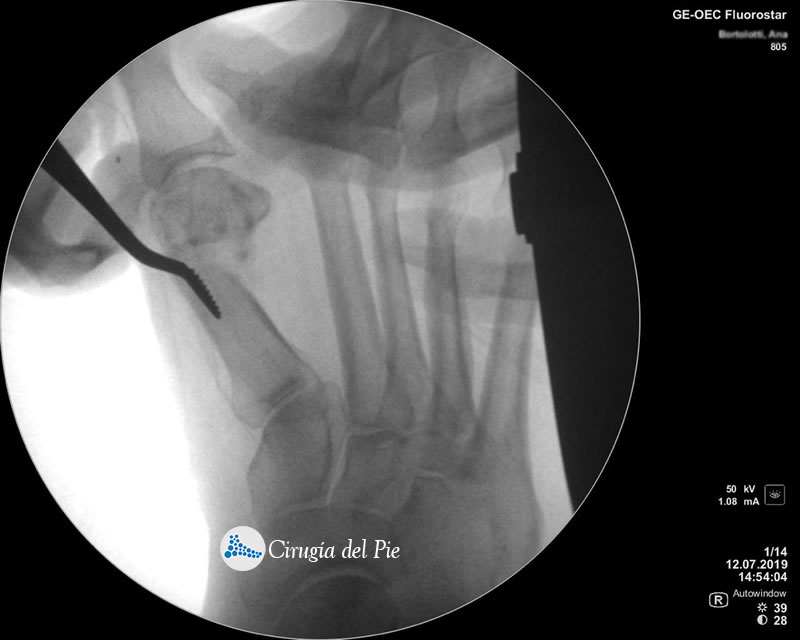

La cirugía Percutánea del pie, también conocida como cirugía MIS (Minimal Incision Surgery), permite realizar procedimientos quirúrgicos a través de pequeñas incisiones en la piel sin gran exposición ni trauma de tejidos.

De esta forma se disminuye el riesgo de complicaciones, como las lesiones de partes blandas, las infecciones y se obtienen menores tiempos operatorios, disminuyendo el dolor y acelerando la vuelta a la vida habitual.

Cirugia Percutanea Dr Masaragian